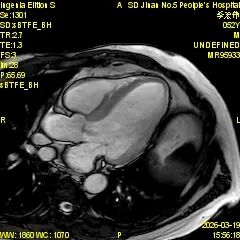

为进一步提升心血管疾病精准诊断水平,满足临床诊疗和患者就医需求,济南市第五人民医院影像科精心筹备、多措并举,顺利开展心脏磁共振(CMR)新技术,目前已完成心脏磁共振检查近30例,取得了良好效果,标志着医院心血管影像诊断能力迈上新台阶。

心脏磁共振被誉为评估心脏结构、功能及心肌组织特征的 “金标准”,具有无创、无辐射、多参数、精准度高等优势,可以为心肌病、冠心病、瓣膜病、先天性心脏病等疾病提供全面、客观的影像学依据,对临床制定治疗方案、评估预后具有重要意义。